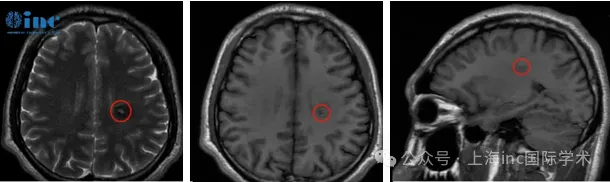

术后当日评估显示患者吞咽与咳嗽功能正常,右上肢轻度无力,其余肢体活动无障碍。术后第四天可实现自主下床活动。根据临床规律,功能区海绵状血管瘤患者需经历短期(数周)生活自理能力恢复与长期(数月到一年)神经功能完全康复两个阶段。本例患者的快速康复得益于手术精准性及系统化术后康复训练。